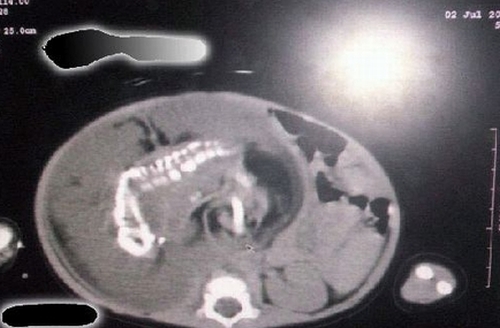

O fetiţă de numai un an din Arabia Saudită este însărcinată. Nu este o glumă proastă, ci rezultatul cercetărilor unor medici din Arabia Suadită. Radiografiile făcute de doctori au demonstrat că bebeluşul îl poartă în pântece pe propriul frate.

Medicii au reuşit să explice şi procesul biologic care a condus la această dramă, potrivit www.momlogic.com. Iniţial, în uterul mamei au existat doi embrioni, dintre care numai unul s-a dezvoltat normal. Din cauza unei anomalii, celălalt a crescut în interiorul bebeluşului. Cu alte cuvinte, fetiţa este însărcinată cu fratele ei geamăn.

Medicii din Arabia Saudită au făcut publice şi radiografiile care demonstrează că, într-adevăr, în abdomenul fetiţei evoluează o sarcină. În prezent, doctorii încearcă să găsească cea mai bună metodă de a-i salva viaţa copilului.

Până în prezent, numai 51 de astfel de cazuri au fost înregistrate în lumea întreagă.